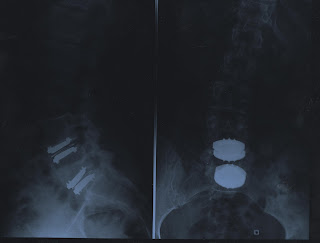

...' tu que te queixas de dores nas costas mas não tens nada', apresento-lhe a Brandia (lombar), a Urraca (lombar), a Maria (cervical) e a outra protese (cervical e que ainda não tem nome e aceitam-se sugestões).